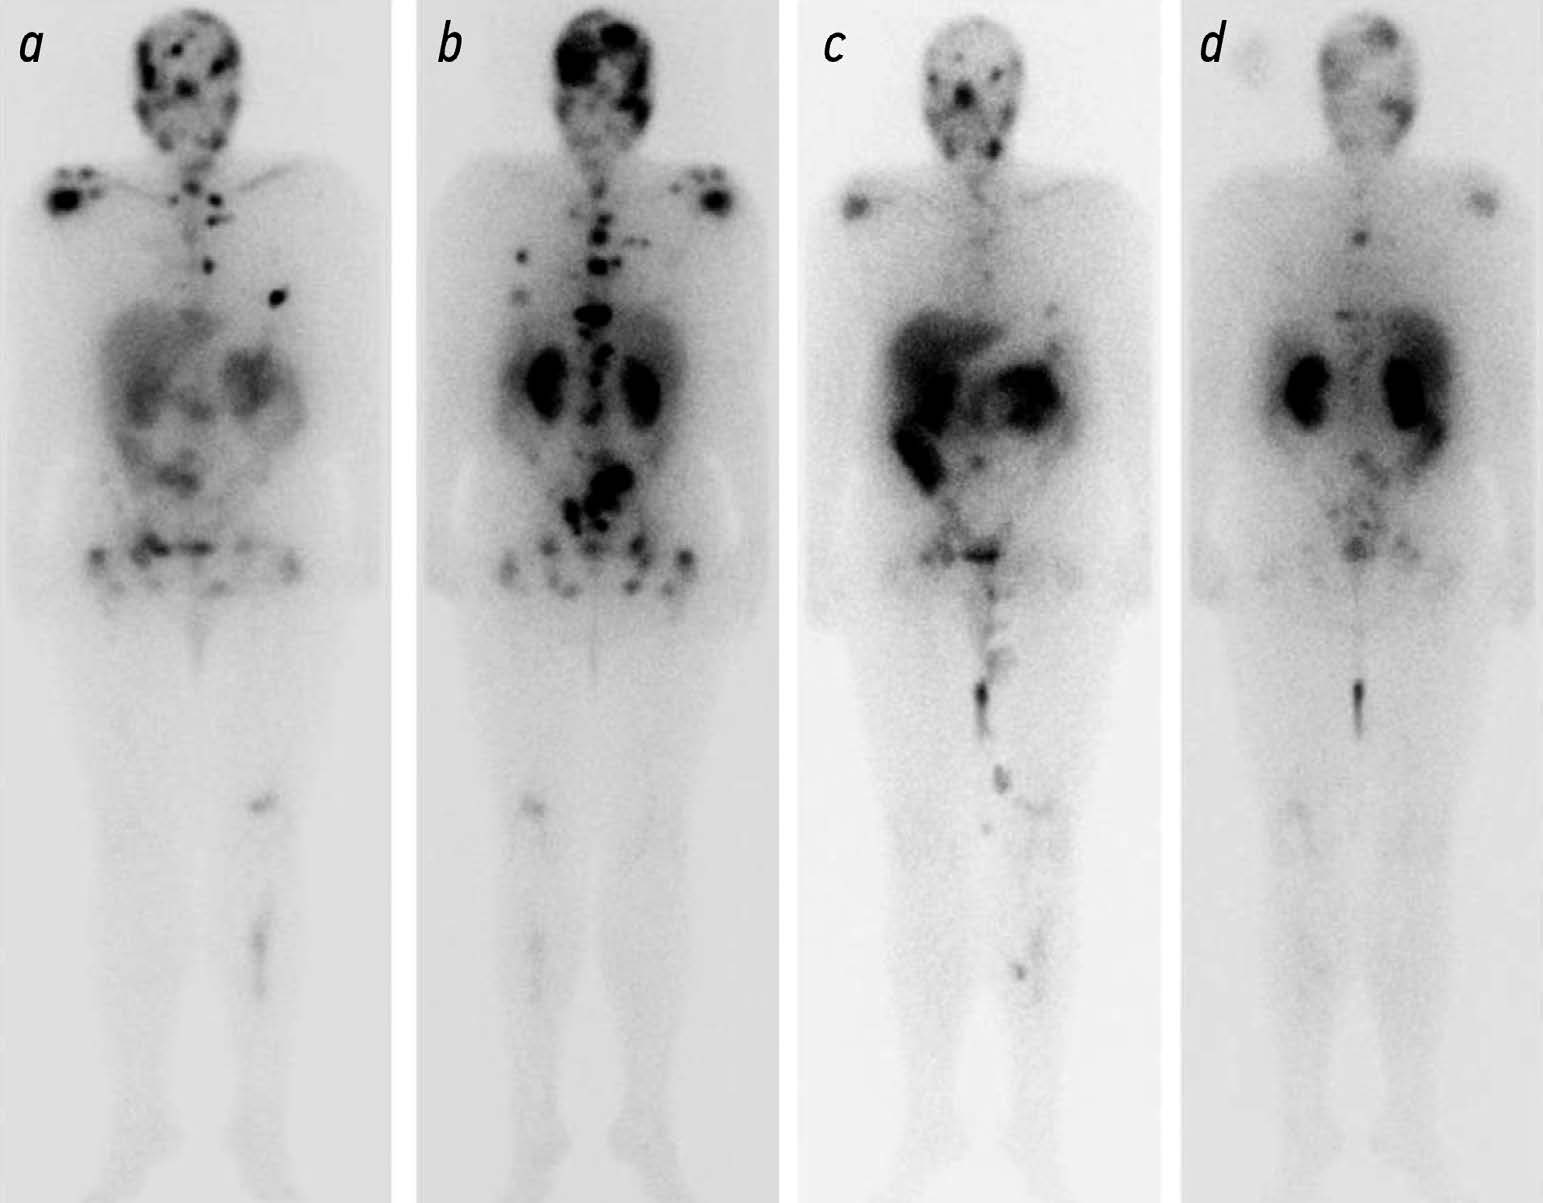

Возможности лучевых методов диагностики метастазов в кости кастрационно-резистентного рака предстательной железы (обзор литературы)

Аннотация

Метастатический кастрационно-резистентный рак предстательной железы (мКРРПЖ) — это прогрессирование опухолевого процесса при формировании невосприимчивости к андроген-депривационной терапии. Частота появления метастазов в костях у таких пациентов достигает 90%. В диагностике мКРРПЖ широко используют лучевые методы исследований. Компьютерная томография и магнитно-резонансная томография обладают преимуществами в анатомической визуализации, однако имеют ограничения в оценке эффективности лечения заболевания. Сцинтиграфию применяют для скрининга метастатического поражения костей скелета, но при этом затруднён анализ прогрессирования заболевания. Позитронно-эмиссионную томографию (ПЭТ), совмещённую с компьютерной томографией, и однофотонную эмиссионную компьютерную томографию используют для раннего выявления местного или системного распространения рака предстательной железы. Информация о количестве поглощённого радиофармпрепарата (РФП) с помощью ПЭТ-визуализации простатоспецифичного мембранного антигена используют для прогнозирования эффективности противоопухолевой терапии. С внедрением в практическую деятельность РФП (177Lu-PSMA) открылась перспектива проведения радионуклидной терапии с одновременным определением её эффективности методами гибридной визуализации. Возможности методов лучевой диагностики метастазов в кости представляют особый интерес для изучения и систематизации получаемых данных и разработки показаний для проведения радиолигандной терапии и анализа её эффективности.

Опубликованные данные свидетельствуют о том, что лучевые методы диагностики мКРРПЖ обладают различной чувствительностью и специфичностью, имеют свои преимущества и недостатки, что говорит о необходимости комплексного подхода в их использовании.

Разработка и развитие методик количественной оценки эффективности лечения, выявление прогностических маркёров позволит грамотно выбрать необходимую тактику лечения и облегчит подбор РФП, что приведёт к увеличению общей выживаемости.